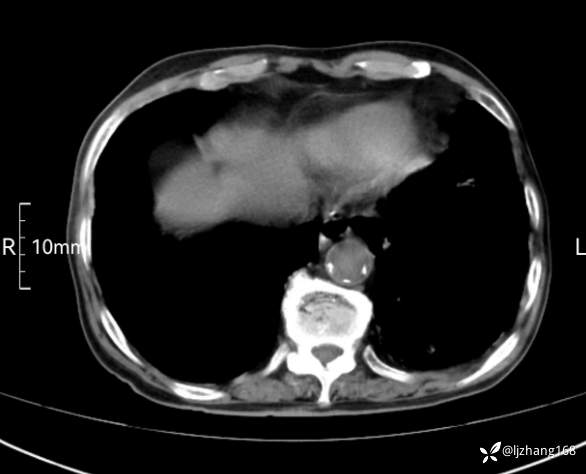

辅助检查:胸部CT:双肺肺气肿,间质性病变,血气分析:PH 7.413, PCO2 29.2mmHg, PO2,81.8mmHg,乳酸 3.3mmol/1,剩余碱-4.0mmol/1,HC03 18.8mmol/1。全血超敏C反应蛋白:超敏C反应蛋白 135.60 mg/L、 白细胞 14x19^9/L,中性粒细胞11.6x10^9/L。